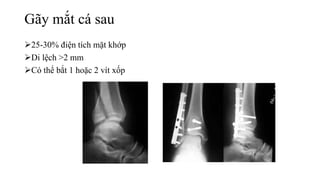

Gãy mắt cá sau

25-30% điện tích mặt khớp

Di lệch >2 mm

Có thể bắt 1 hoặc 2 vít xốp

Gãy mắt cásau 25-30% điện tích mặt khớp Di lệch >2 mm Có thể bắt 1 hoặc 2 vít xốp